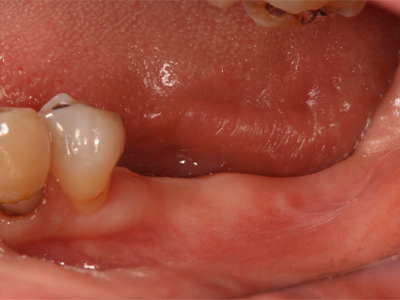

治療前後写真

治療前

治療後

47歳・女性

来院理由

左下の奥歯が痛くて咬めない

治療内容

- ① 抜歯後に診査・シミュレーション

- ② サージカルテンプレートを用い、インプラント埋入+歯槽骨造成を併用(一次手術)

- ③ 3ヶ月後に二次手術(歯肉移植併用)

- ④ 最終補綴装着→メンテナンス移行

治療期間

一次→二次手術まで約3ヶ月、その後最終補綴

費用

1,069,200円

リスク・副作用

口腔清掃・メンテ不足で周囲炎・感染・脱落の可能性

医院コメント

インプラント周囲に厚い角化歯肉を再建し、清掃性を高めて長期安定を図った。